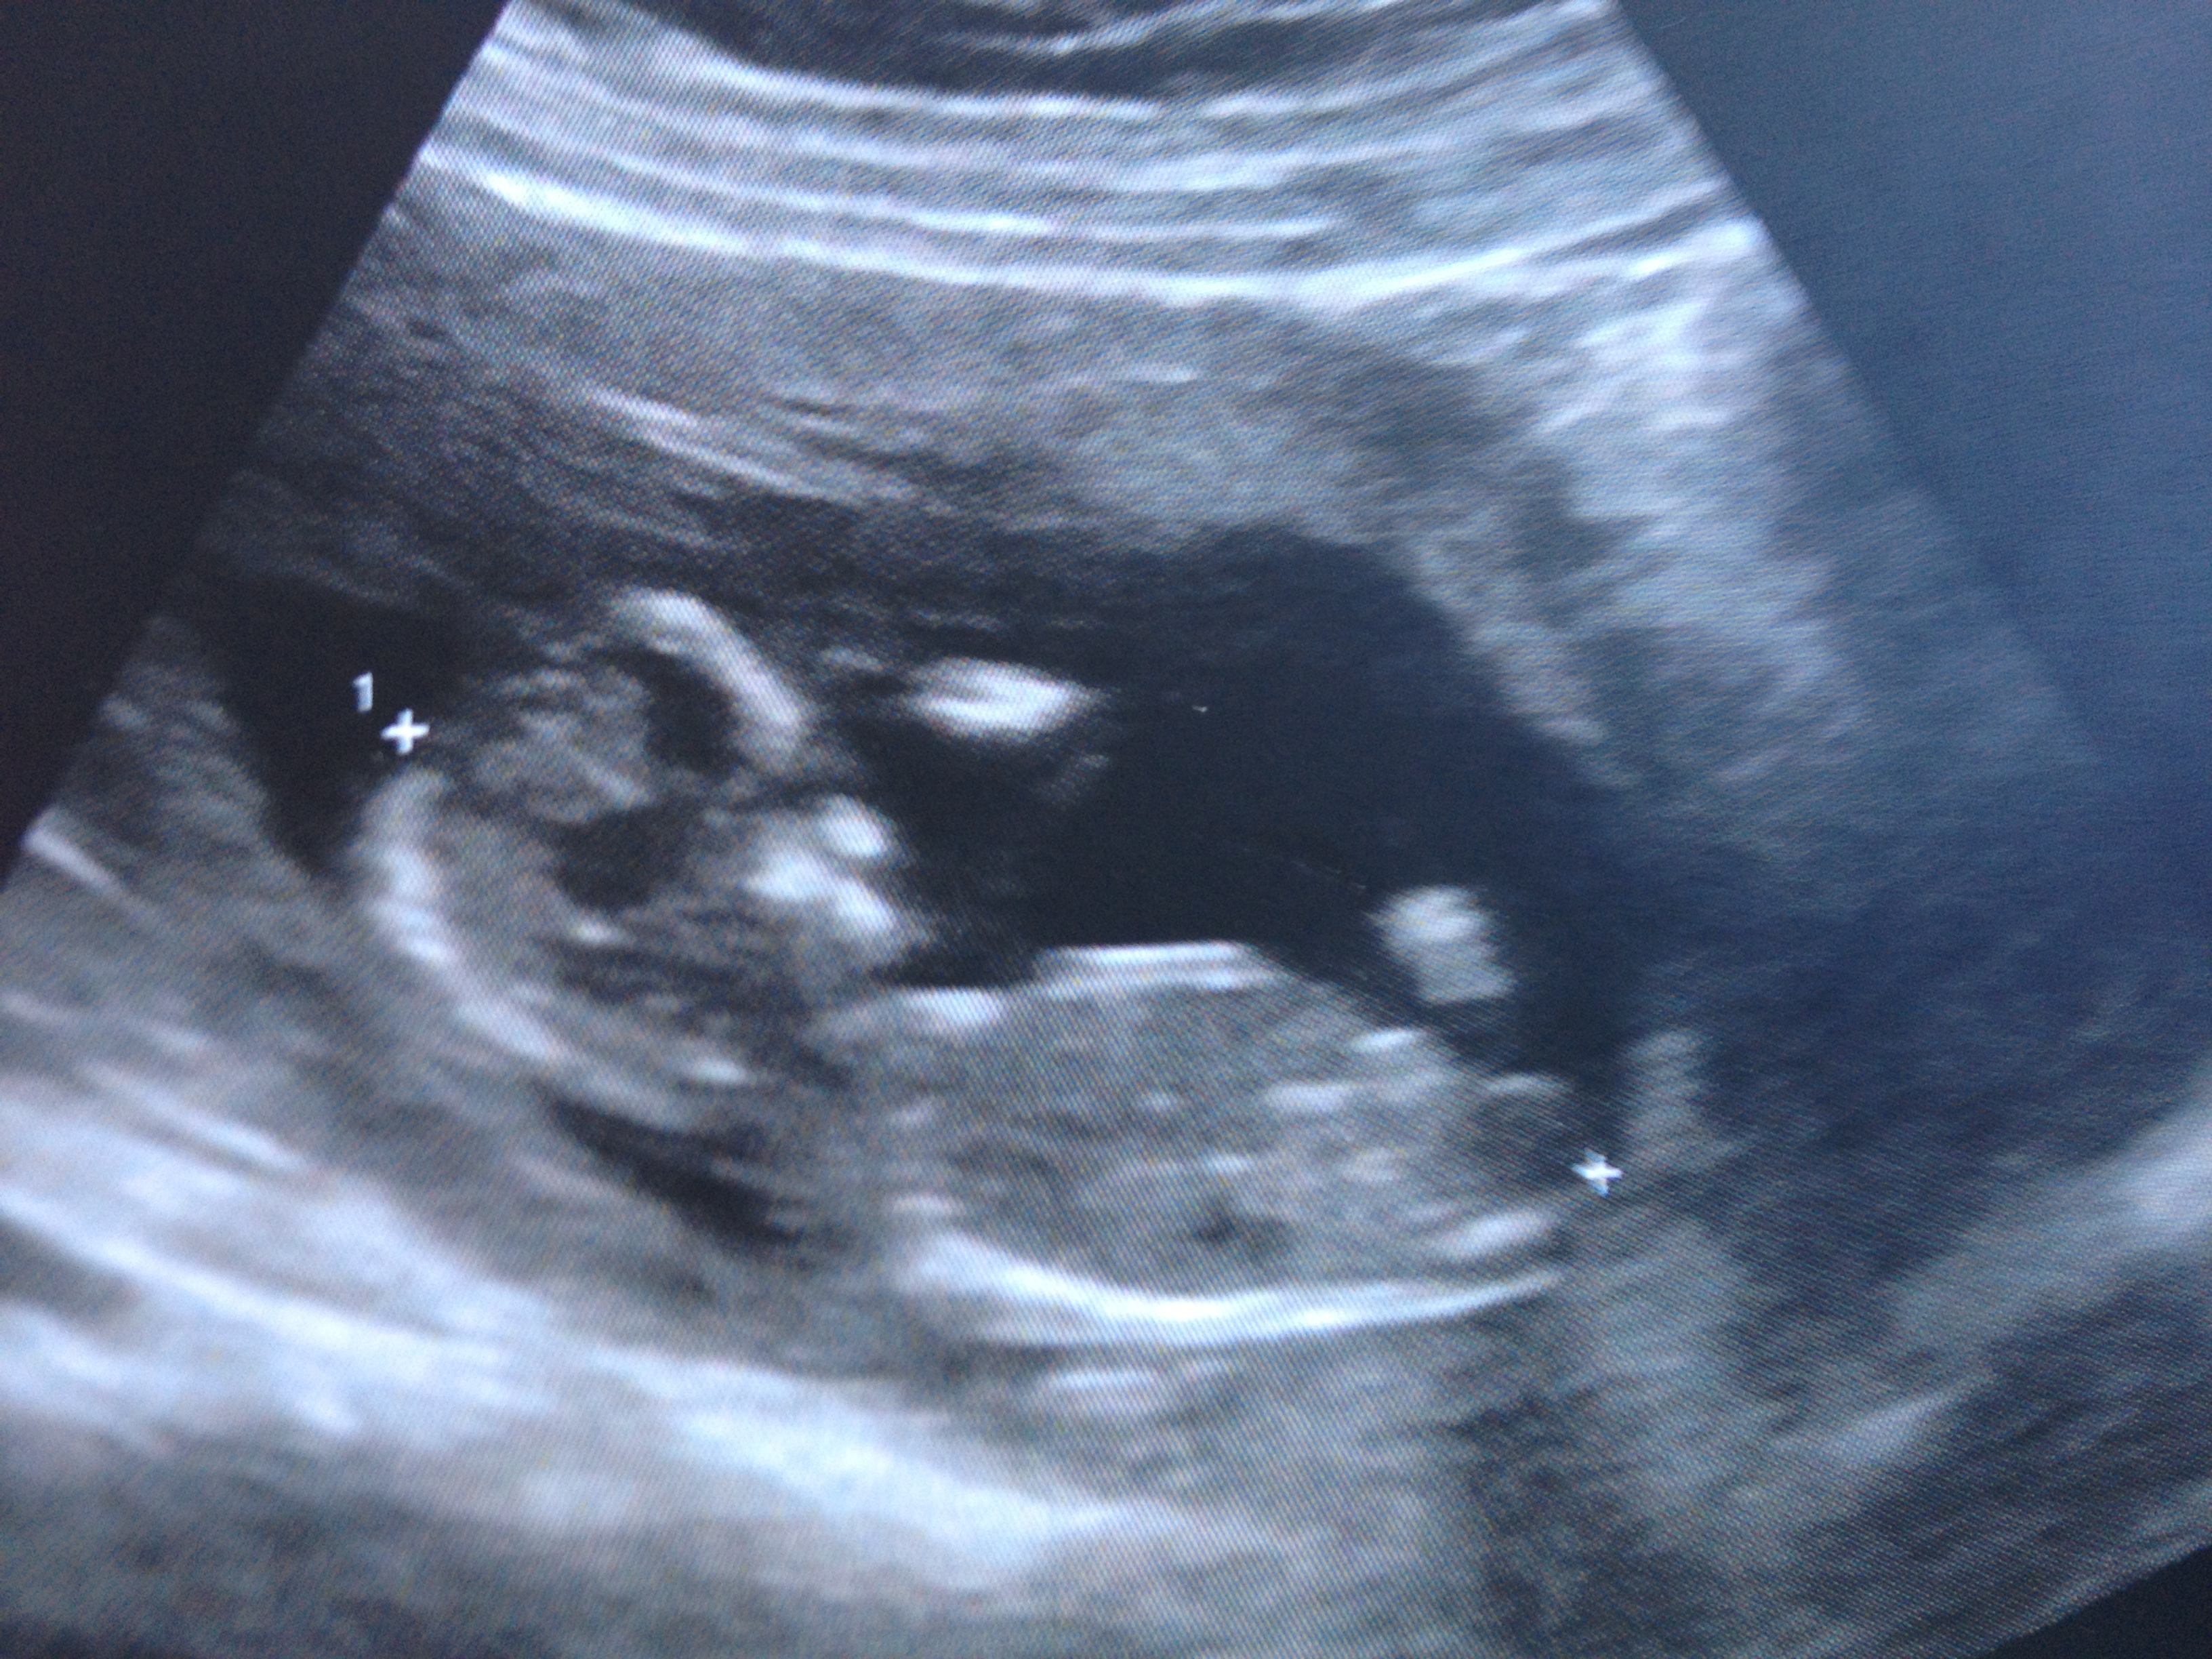

Here is my picture from today. I think it's a girl :D heart beat was 158 BPM so what do you all think? :babyf:? :babym:? :D

Yah girl I think;)

I don't guess skulls. Nub looks short but flat, at gestation, I'd guess girl. It might not have been fully captured though.